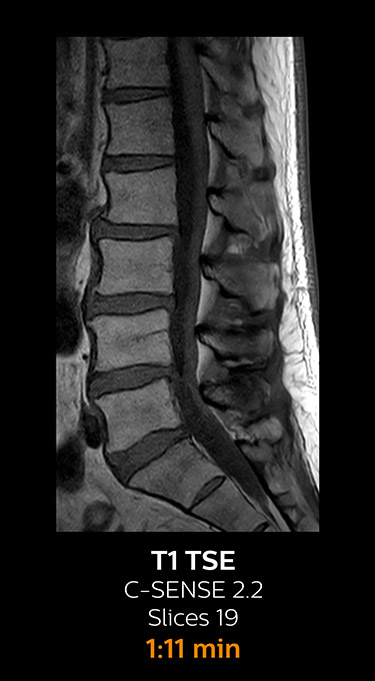

With Compressed SENSE, the scan time for the routine lumbar spine examination at KNC was reduced from 11:41 to 8:17 minutes,

MRI examination of the lumbar spine with Compressed SENSE

Ingenia 3.0T CX

Scan time 8:17 min. (was 11:41 min. without Compressed SENSE)